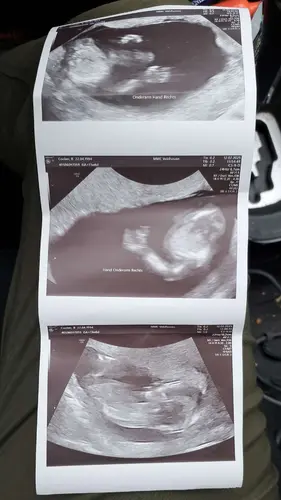

nee dat zijn geen mooie foto’s.. ik krijg ze mee op een stick maar wel veel mooier..

Je exho fotos zijn heel lelijk. Kun je bij jou in het zkh inloggen in je patientdossier? Bij mij stonden hier meer fotos dan degenen die ik mee had gekregen.

Maar de echo’s die jij hebt gekregen zijn wel echt van hele slechte kwaliteit ☹️ de foto’s die ik meekrijg uit het ziekenhuis zijn wel met zorg en aandacht gemaakt. Vervelend voor je! Ik zou het de volgende keer wel gewoon aangeven hoor want dit is niet leuk

Vergeet erbij toe te voegen dat ik zelf nog nooit die mooie duidelijke echofotos heb gehad als dat ik vaak heb gezien van anderen. De mijne zijn altijd bewogen, je ziet wel wat maar gewoon niet zo scherp en zo mooi hoog contrast als wat ik weleens zie.